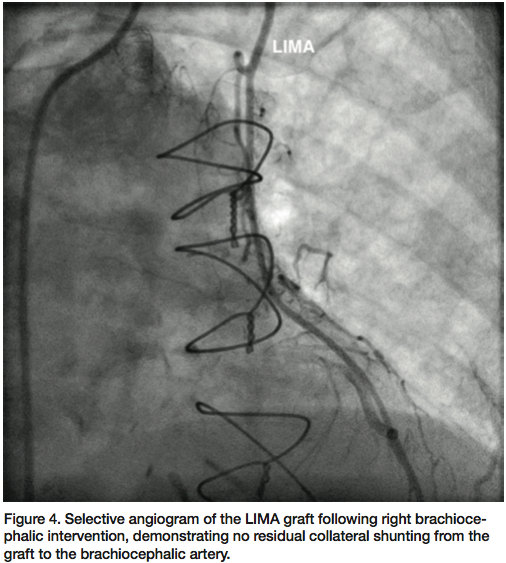

(Fr) and 7 Fr sheaths, respectively. A V-18 wire (Boston Scientific) was advanced with support of a Sterling 4 x 20 mm balloon (Boston Scientific) to cross the right brachiocephalic artery occlusion into the aorta. Selective angiogram through the balloon into the aorta confirmed an intraluminal position in the aortic arch. After serial dilatations, an iCAST (Atrium) 7 x 22 mm covered stent was deployed at the ostium of the right brachiocephalic artery at 14 atm, with good expansion. Final angiogram after post-dilation confirmed brisk flow through the stented segment (Figure 3). Subsequent angiogram of the LIMA graft revealed brisk

flow through the graft into the distal LAD (Figure 4). Follow-up carotid ultrasound showed peak systolic and diastolic velocities in the right internal carotid artery to be 149 and 36, respectively, with antegrade flow in the vertebral artery.